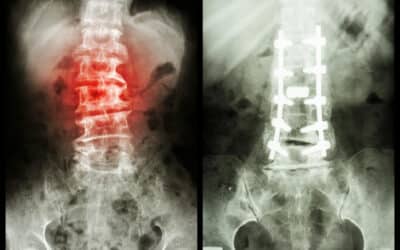

What Are The Chances Of Paralysis Post-Spine Surgery

What Are The Chances Of Paralysis Post-Spine Surgery? Spine surgery can significantly alleviate pain, enhance mobility, and dramatically improve your quality of life. Like any surgical procedure, spine surgery carries inherent risks, although serious neurological...